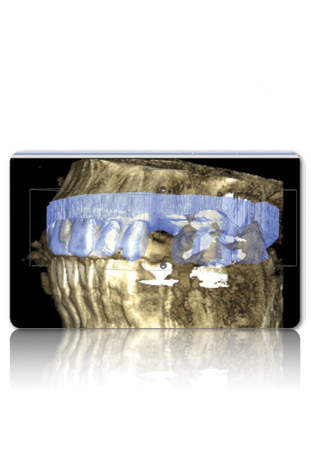

Figure 3 Examples of using digital workflow to import restoration data and plan implant treatment: the intraoral scan (IOS) data pinned to the CBCT (Fig 3); the designed ideal restoration being imported into the CBCT (Fig 4); the implant placed with the restoration and IOS toggled off (Fig 5).

Figure 4 Examples of using digital workflow to import restoration data and plan implant treatment: the intraoral scan (IOS) data pinned to the CBCT (Fig 3); the designed ideal restoration being imported into the CBCT (Fig 4); the implant placed with the restoration and IOS toggled off (Fig 5).

Figure 5 Examples of using digital workflow to import restoration data and plan implant treatment: the intraoral scan (IOS) data pinned to the CBCT (Fig 3); the designed ideal restoration being imported into the CBCT (Fig 4); the implant placed with the restoration and IOS toggled off (Fig 5).

Although workflows can vary, in many implant cases, typically a CBCT scan of the area of concern is made. Then, with an intraoral scan or digital version of a model or impression, the practitioner begins working with the design software of the particular intraoral scan or CBCT system being used (Figure 3 through Figure 5). The edentulous area or area where teeth are to be extracted can then be thoroughly evaluated. Ideal restorations can then be previsualized or treatment planned from both an esthetic and functional standpoint. Once this is done, the intraoral information is pinned or overlaid onto the CBCT scan. The restoration(s) can then be imported into the software system, toggled on or off—ie, shown or not—and the underlying bone evaluated.3